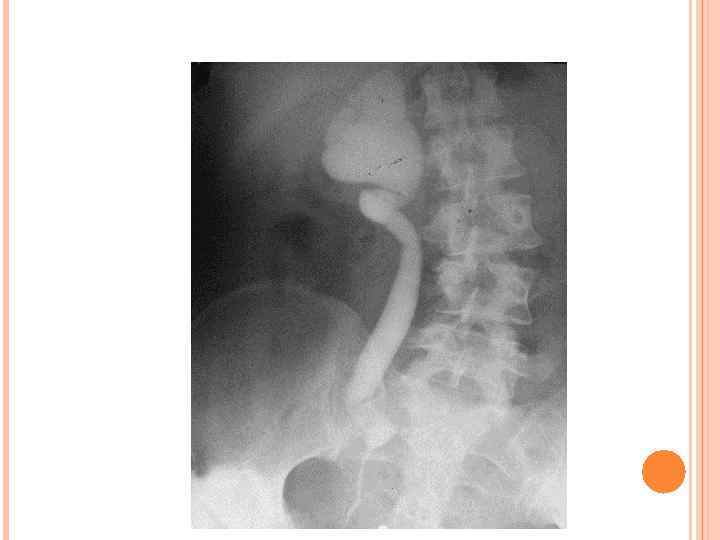

Агенезия легкого - отсутствие легкого и главного бронха. Аплазия - отсутствие легкого или его части при наличии сформированного или рудиментарного бронха. Агенезия возникает в результате прекращения роста бронхолегочных почек на 4 -й неделе внутриутробной жизни, аплазия - при задержке их развития на 5 -й неделе. При двусторонней агенезии и аплазии легких дети нежизнеспособны. 5. Аплазия легкого 4. Гипоплазия легкого Ангиопульмонограмма. Отсутствует правая ветвь легочной артерии.

Агенезия легкого - отсутствие легкого и главного бронха. Аплазия - отсутствие легкого или его части при наличии сформированного или рудиментарного бронха. Агенезия возникает в результате прекращения роста бронхолегочных почек на 4 -й неделе внутриутробной жизни, аплазия - при задержке их развития на 5 -й неделе. При двусторонней агенезии и аплазии легких дети нежизнеспособны. 5. Аплазия легкого 4. Гипоплазия легкого Ангиопульмонограмма. Отсутствует правая ветвь легочной артерии.